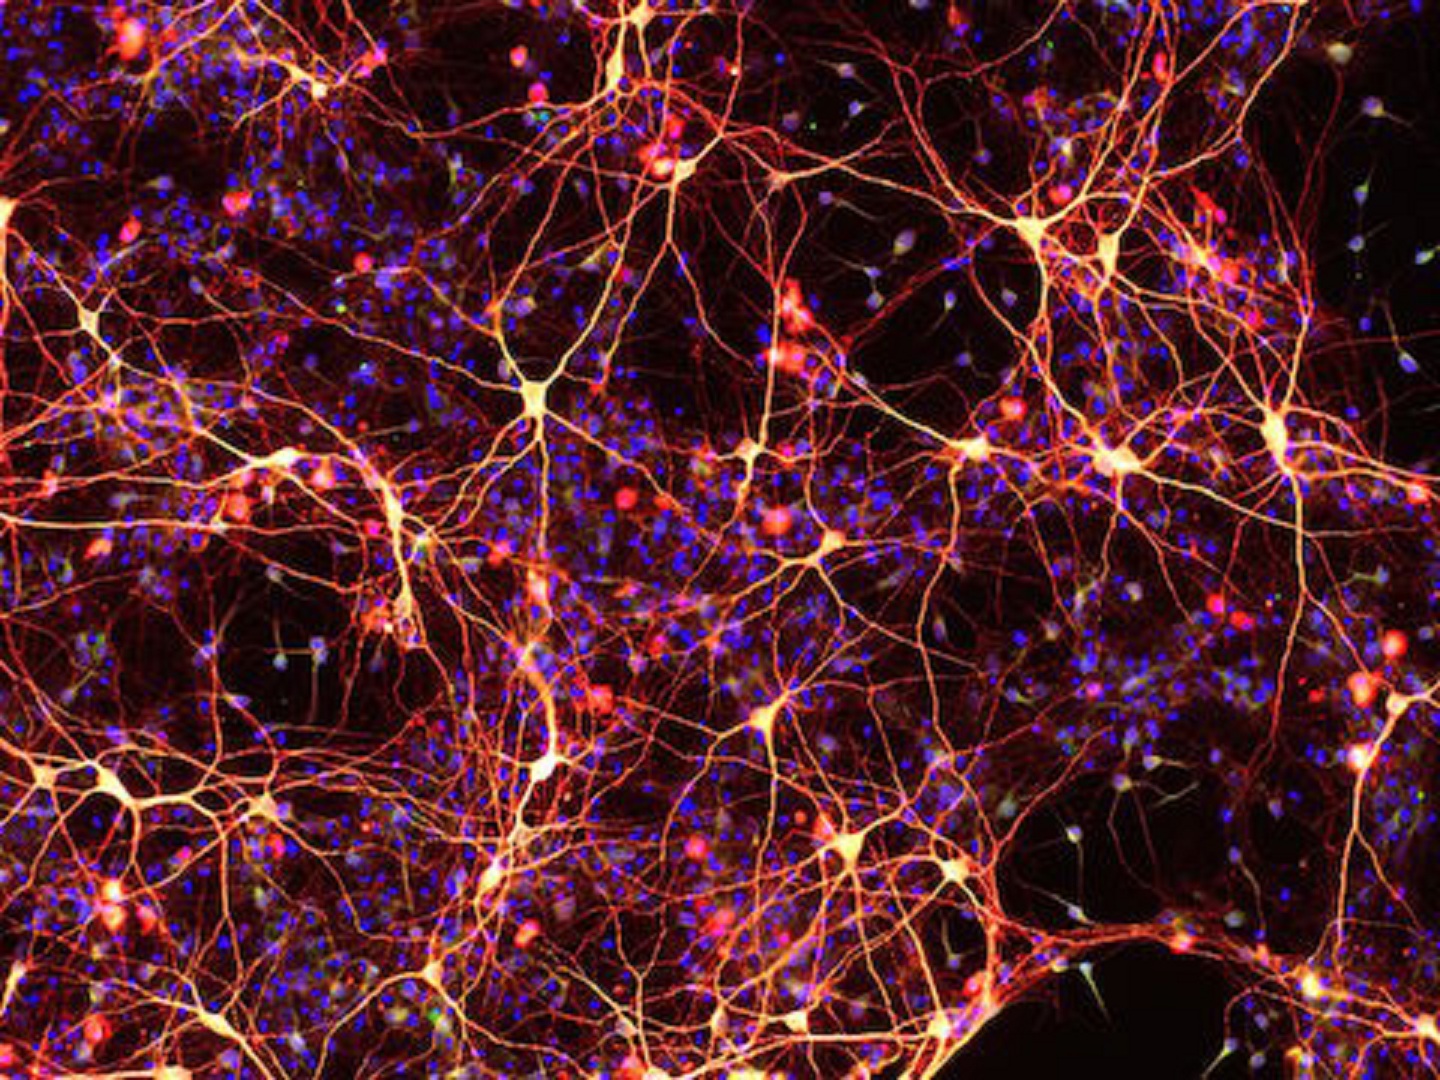

Neuronas creadas a partir de células madre neuronales químicamente inducidas. Imagen: M. Zhang. Fuente: Institutos Gladstone.

En el segundo estudio, cuyo autor es el investigador postdoctoral Mingliang Zhang, y que se ha publicado en Cell Stem Cell, los científicos crearon células madre neurales a partir de células de piel de ratón utilizando un enfoque similar.

El cóctel químico de nuevo consistió en nueve moléculas, algunas de las cuales se superponen con las utilizadas en el primer estudio. Durante diez días, el cóctel cambió la identidad de las células, hasta que todos los genes de las células de la piel se apagaron y los genes de células madre neurales se activaban gradualmente.

Cuando se trasplantaron a ratones, las células madre neuronales evolucionaron espontáneamente en los tres tipos básicos de células cerebrales: neuronas, oligodendrocitos y astrocitos. Las células madre neuronales también fueron capaces de auto-replicarse, lo que es ideal para el tratamiento de enfermedades neurodegenerativas o lesiones cerebrales.

"Estas células madre neurales podrían emplearse un día para la terapia de reemplazo celular en enfermedades neurodegenerativas como el parkinson y el alzheimer", dice el co-autor Yadong Huang. "En el futuro, podríamos incluso imaginar el tratamiento de pacientes con un cóctel de fármacos que actúe sobre el cerebro o la médula espinal, rejuveneciendo las células del cerebro en tiempo real."

En el segundo estudio, cuyo autor es el investigador postdoctoral Mingliang Zhang, y que se ha publicado en Cell Stem Cell, los científicos crearon células madre neurales a partir de células de piel de ratón utilizando un enfoque similar.

El cóctel químico de nuevo consistió en nueve moléculas, algunas de las cuales se superponen con las utilizadas en el primer estudio. Durante diez días, el cóctel cambió la identidad de las células, hasta que todos los genes de las células de la piel se apagaron y los genes de células madre neurales se activaban gradualmente.

Cuando se trasplantaron a ratones, las células madre neuronales evolucionaron espontáneamente en los tres tipos básicos de células cerebrales: neuronas, oligodendrocitos y astrocitos. Las células madre neuronales también fueron capaces de auto-replicarse, lo que es ideal para el tratamiento de enfermedades neurodegenerativas o lesiones cerebrales.

"Estas células madre neurales podrían emplearse un día para la terapia de reemplazo celular en enfermedades neurodegenerativas como el parkinson y el alzheimer", dice el co-autor Yadong Huang. "En el futuro, podríamos incluso imaginar el tratamiento de pacientes con un cóctel de fármacos que actúe sobre el cerebro o la médula espinal, rejuveneciendo las células del cerebro en tiempo real."